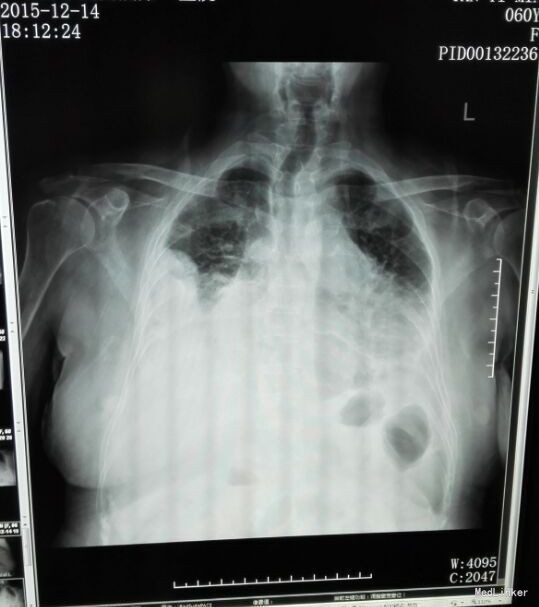

患者入院后予“美洛西林舒巴坦”抗感染,当天晚上出现明显气促,伴右后下背痛,无明显发热,当时复查胸片示: 1、双下肺炎症、双侧胸腔积液,同2015.12.13前片比较,考虑右侧胸腔积液明显增多,部分包裹,建议CT进一步检查。血气分析未见明显异常,2015-12-14 复查急诊血常规:白细胞计数 24.290(10E9/L)↑,淋巴细胞计数 0.750(10E9/L)↓,中性粒细胞比例 0.930↑,血红蛋白浓度 104.000(g/L)↓,中性粒细胞计数 22.590(10E9/L)↑,红细胞计数 3.500(10E12/L)↓,血小板计数 466.000(10E9/L)↑,单核细胞计数 0.920(10E9/L)↑;急诊肾功(三项):尿素氮 8.450(mmol/L)↑;急诊电解质(K/Na/Cl):钠 128.700(mmol/L)↓,氯 87.100(mmol/L)↓; 2015-12-14胸部及上腹部CT平扫+增强示:1、两中下肺多发炎症,部分萎陷。建议治疗后复查。2、双侧胸腔积液(右著);心包少量积液。3、结合病史,右输尿管术改变;右侧双J管置入术后。右肾、输尿管上段扩张、积水,右肾周感染并少许积气;左肾结石。4、脂肪肝。5、胆、脾、胰未见异常。因CT提示肺部大片实变,包裹性积液(量少),考虑重症肺炎可能,于2015-12-14将抗生素升级为“亚胺培南西司他丁 1.0 q8h、万古霉素 50万U q12h、伏立康唑 0.2 q12h”三联,同时予“甲强龙”抗炎等治疗。经治疗,患者气促症状逐渐缓解,咳嗽、咳痰、右后背疼痛好转,无发热,精神、胃纳较前改善。因B超定位下胸水量少,暂未予胸穿。2015-12-17复查胸部+上腹部CT平扫示:1、双中下肺炎炎症较前吸收好转,右侧胸腔积液较前略有减少,左侧胸腔积液现已基本吸收。2、胸、腹主动脉粥样硬化;心包少量积液(大致同前)。纵膈内临界肿大淋巴结。3、右输尿管术改变;右肾、输尿管上段扩张、积水,右肾周慢性感染(原右肾周积气消失);左肾结石。4、轻度脂肪肝。少量腹水。5、胆囊内斑片状高密度影,考虑胆汁淤积。2015-12-19 复查血常规:白细胞计数 18.160(10E9/L)↑,中性粒细胞比例 0.918↑,血红蛋白浓度 105.000(g/L)↓,中性粒细胞计数 16.670(10E9/L)↑,红细胞计数 3.560(10E12/L)↓,血小板计数 396.000(10E9/L)↑,淋巴细胞比例 0.037↓,红细胞压积 0.305↓,单核细胞计数 0.780(10E9/L)↑;降钙素原 2.000(ng/ml)↑;急诊肾功(三项):肌酐 146.000(umol/L)↑,尿素氮 19.580(mmol/L)↑。2015-12-20患者精神较前明显变差,伴纳差、乏力,气促较前加重,2015-12-20再次复查血常规:白细胞计数 33.230(10E9/L)↑,中性粒细胞比例 0.967↑,红细胞计数 3.350(10E12/L)↓,中性粒细胞计数 32.130(10E9/L)↑,血红蛋白浓度 99.000(g/L)↓,单核细胞比例 0.016↓,淋巴细胞比例 0.016↓,红细胞压积 0.293↓;2015-12-20 急诊肾功(三项):肌酐 125.000(umol/L)↑,尿素氮 15.960(mmol/L)↑;降钙素原 0.836(ng/ml)↑;复查胸片示:1、同2015.12.17胸部CT比较,考虑右侧胸腔积液较前有所增多,大部分为包裹性积液,新发左侧胸腔少量积液;右肺情况显示不清,左下肺炎症。2、心影增大,结合CT考虑心包积液;主动脉粥样硬化。遂行胸腔穿刺术,抽出400ml黄白色脓性胸水,胸水常规:PH6.0,WBC54600*10E6/l,中性粒0.97,胸水生化:乳酸脱氢酶 2221.000(U/L);葡萄糖 1.180(mmol/l),总蛋白 24.000(g/l),腺苷脱氨酶 154.000(U/L),氯 106.800(mmol/L)。符合脓胸改变,予右侧胸负压腔闭式引流,同时予“庆大霉素16万u”冲洗,将抗生素降级为莫西沙星片口服,患者症状明显好转,12.24复查胸片及CT胸腔积液及肺炎均较前明显好转。